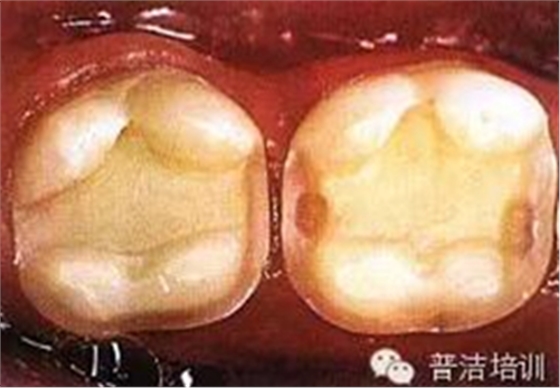

三、牙體預(yù)備完成,,邊緣預(yù)備短斜面(45度),短斜面這點(diǎn)很多書上沒具體說,想想還是有必要的,但在金屬嵌體和瓷嵌體就沒必要了。其實(shí)預(yù)備這一步驟沒什么高深莫測的,多加訓(xùn)練,端正態(tài)度就可以。

四、如果在預(yù)備過程中,有比較明顯的倒凹存在時(shí),可以在軸壁以及軸髓線角處涂一層蠟,并可作為樹脂水門汀預(yù)留在空間,但不可涂抹過多。